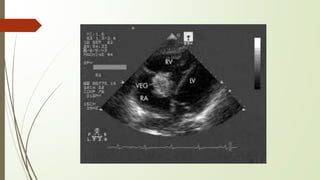

ECHOCARDIOGRAPHY